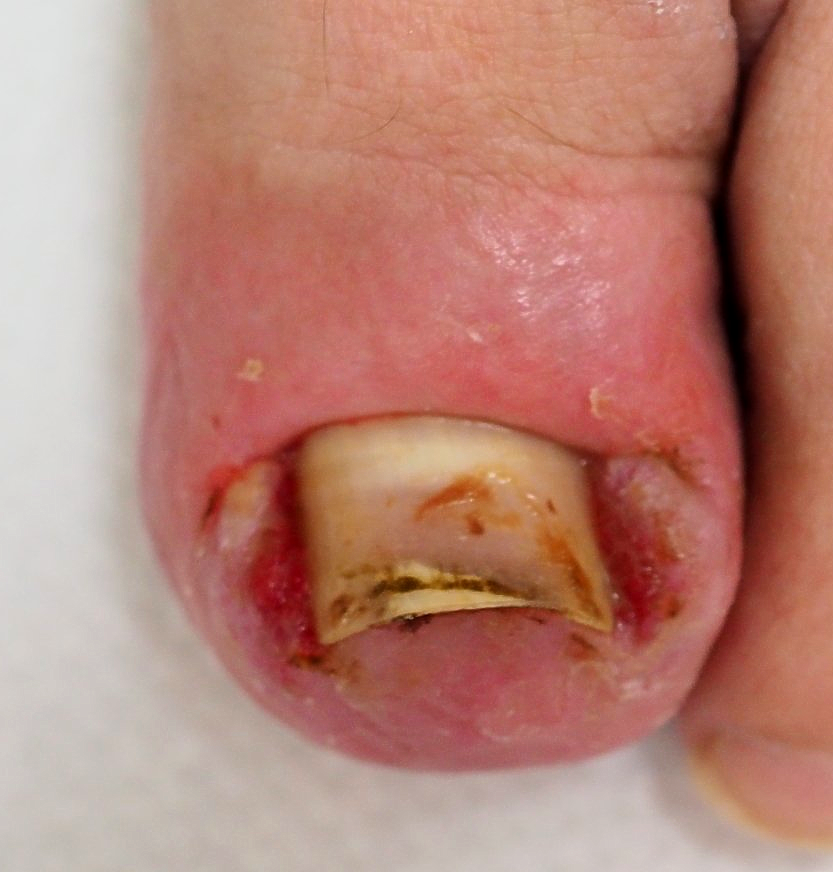

🔴Bild 3: der geborgene Nagelspan Bild 4: in dieser Position grub sich der Nagel durch das Gewebe

Hühnerauge subungual (unter der Nagelplatte)

Bild 1

die Ausgangssituation,

Bild 2

die geöffnete Nagelplatte unmittelbar nach der Entfernung des Hühnerauges